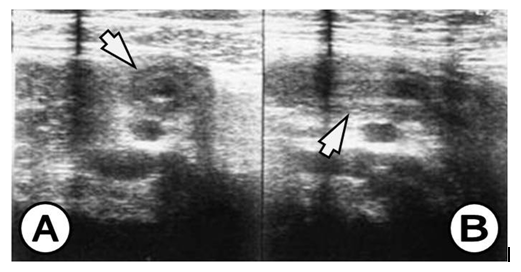

The appendix on US study is demonstrated by: hypo echoic lumen, hyper echoic mucosa, iso echoic lamina propria, hyper echoic submucosa, hypo echoic muskularis and hyper echoic serosa. The increased size of the appendix is a sign for phlegmonous or gangrenous appendicitis (Figure 1). The present appendicolith is demonstrated as hyper echoic mass that fills in the lumen and gives acoustic shadow (Figure 2B). When the appendicolith should be visualized, the wall thickness and the compressibility are not the features for making the diagnosis of acute appendicitis. The gangrenous appendicitis has changes in echogenity in all layers and the same are with the uniform echogenity and cannot be distinguished (Figure 3A). If the ill defined or hypo echoic mass is seen that surrounds the appendix that presents the periappendiceal inflammation (Figure 4). The ill defined appendiceal wall is suggestible, but not diagnostic for the periappendiceal process. The fluid presence into the appendiceal surrounding, with appendiceal wall echogenity changes is US feature for perforation (Figure 3B). The positive lymph nodes are oval hypo echoic and they don’t change the shape on compression.

Figure 4 (A) Coronal view, appendix with thickened wall and surrounding infiltration, (B) Saggital view, appendix with thickened wall and surrounding infiltration, US finding for appendiceal phlegmon.